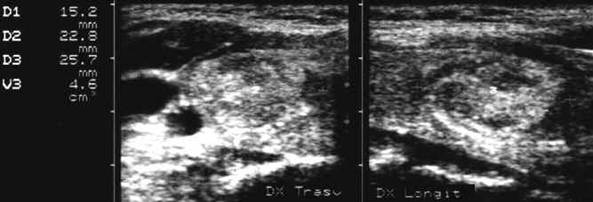

Nodul hipoecogen, neomoge, cu contur net, de 15x21x27 mma (4 cc) in lobul drept.

Examen citologic prin citoaspirate: nodul hiperplazic.